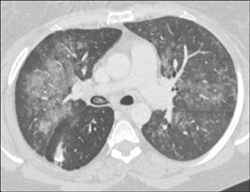

Pulmonary Atresia With A Stent in the Right Pulmonary Artery